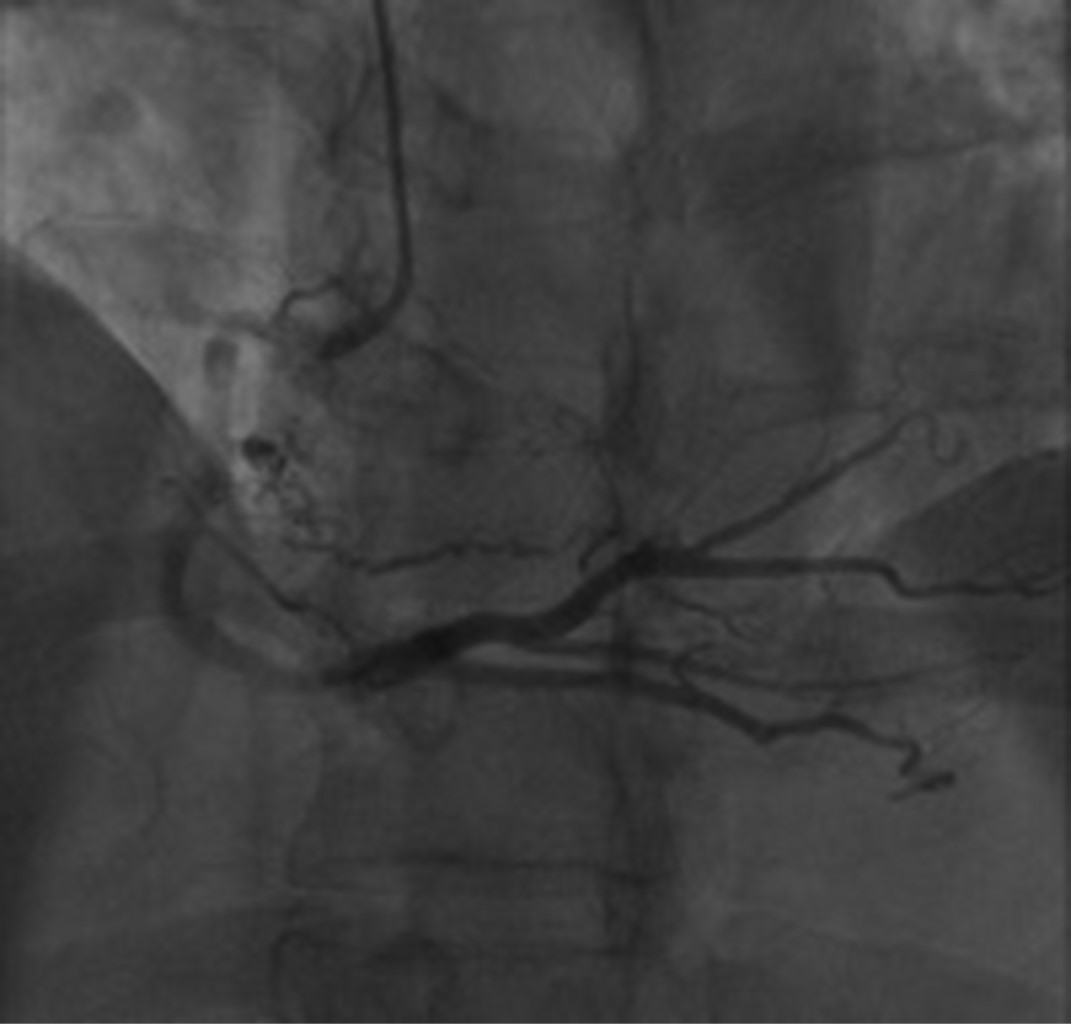

Introducción: los mixomas cardiacos son las neoplasias primarias más frecuentes del corazón. La ubicación más común es la aurícula izquierda (75%), seguido de la aurícula derecha (15-18%) y ventrículo izquierdo. Pueden presentarse con la tríada de síntomas obstructivos, embólicos y constitucionales. Caso 1: varón de 59 años en seguimiento por linfoma cutáneo no Hodgkin de linfocitos T, que padecía disnea progresiva y presentaba una masa localizada en la aurícula derecha. Se realizó resección del tumor y reemplazo de la válvula mitral debido a insuficiencia mitral severa. La histopatología confirmó el diagnóstico de mixoma. Caso 2: mujer de 61 años que consulta por trombosis en vena basílica, cefálica y yugular derecha. Un ecocardiograma mostró una masa cardiaca de 80 × 40 mm en la aurícula derecha. En el informe histopatológico se informó un mixoma cardiaco con el diámetro mayor de 7.5 cm. Fue dada de alta nueve días después de la cirugía. Conclusión: podría haber una presentación inusual de mixoma auricular que ocurra simultáneamente con una neoplasia de diferente linaje. Debe sospecharse mixoma auricular, incluso en ubicaciones inusuales e independientemente de la enfermedad neoplásica concomitante. Los fenómenos embólicos, como la primera presentación, pueden inducir a error; aunque algunos parámetros y puntuaciones pueden ser predictores útiles.

Figura 2